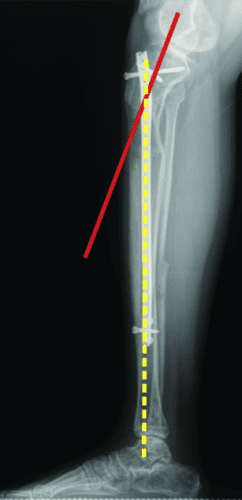

过早合并示意图1

图1:延长量细微差异

过早合并示意图2

图2:X光片确认诊断

8 轴向偏差

继发于延长的轴向偏差或畸形并不是一个罕见的问题。它通常是可以预防的。使用转子钉更有可能出现内翻畸形。出于这个原因,我更喜欢使用梨状肌入口钉。在股骨近端延长术中,如果截骨术是在骨头紧贴指甲周围的地方进行的,则内翻成角的可能性不大。如果需要进行更近端的股骨截骨术,内侧阻断螺钉可以防止内翻偏斜。

轴向偏斜是胫骨中更常见的问题。胫骨往往会延长成外翻和外翘。为防止这种情况,钉子应插入正确的起点,该起点非常高,并且尽可能靠后,在胫骨的外侧,并在额平面的膝盖中心。如果指甲与截骨术上方的外侧皮层之间有空间,则应在该空间中插入阻挡螺钉。如果指甲与后皮层之间有空间,则在那里插入另一个阻挡螺钉。我设计了 STRYDE 钉子,通过提供第三个近端锁定螺钉(P2.2 只有两个)来抵抗轴向偏差。如果遵循所有这些预防措施,则不会随着延长而出现屈曲或外翻畸形。

敲击(外翻)鞠躬(内翻)

屈曲(procurvatum)

在外部机构胫骨身材延长并出现双侧并发症的患者。他发展了胫骨和 Abu/a 延迟结合,右侧是敲击 {外翻),左侧是弓形 {内翻),两侧是 f1exion {procurvatum}。我们在手术室使用临时外部斧头机对两侧进行了急性矫正,并放置了新的胫骨杆。我们在 Abu/a 延迟结合上放置了逆行杆。